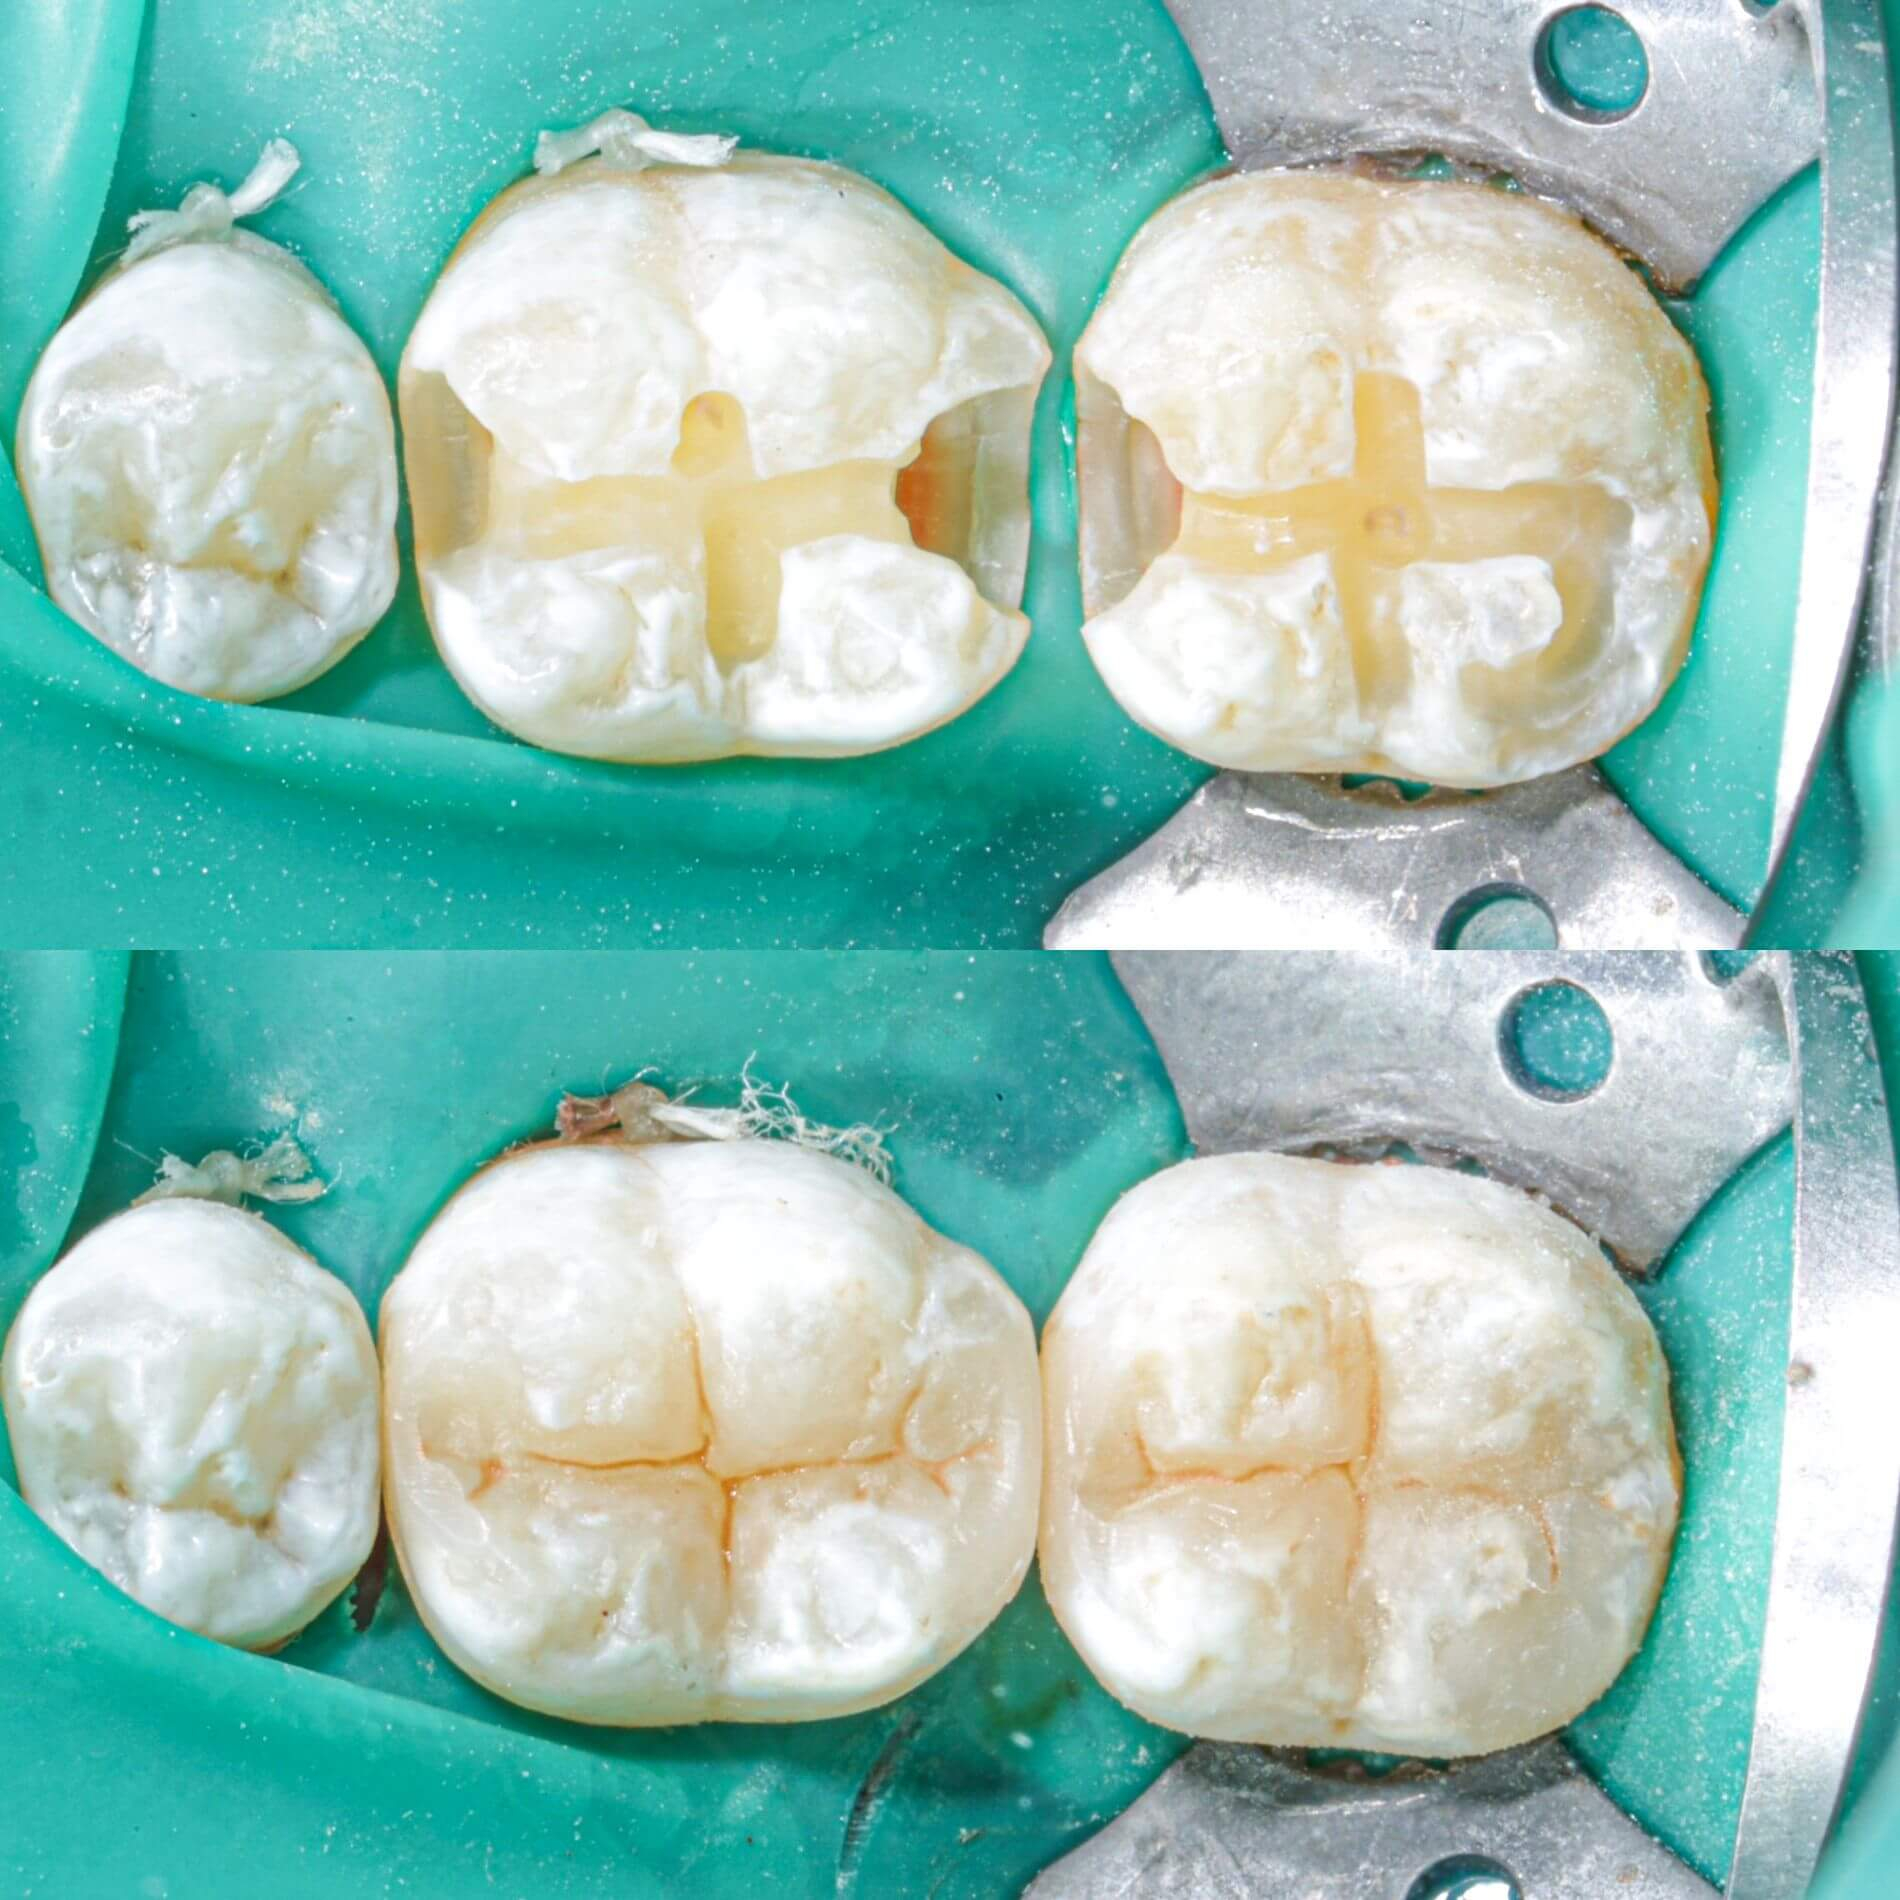

Пломбування зубів - процедура доволі земна та стандартна. Зубна порожнина заповнюється пломбувальним матеріалом та здійснюється відновлення анатомічної форми зуба. Завдяки цьому нам вдасться зберегти твій зуб і запобігти поширенню шкідливих бактерій вглиб зубу та далі по ротовій порожнині. Встановлення пломби - це оптимальний спосіб лікування карієсу і фінальний етап лікування пульпіту. Процес пломбування зуба відрізнятиметься в залежності від техніки та призначення пломби.

Колись давним-давно, в земних стоматологіях ставили цементні пломби. Думаємо, цей незабутнє відчуття «піску» після процедури багатьох переслідує досі. На щастя, ці часи минули, і тепер для твоїх зубів нас є крутий фотополімерний матеріал з космічними наночастинками. Він не тільки дуже міцний, а й гарно світиться ночами(це звісно ж жарт). Це просто найінноваційніший пломбувальний матеріал з усіх, що існуюють на ринку.

- Постійні. В Космічній стоматології Драганчука ми застосовуємо дуже крутий пломбувальний матеріал з наночастинками. За міцністю він не поступається найміцнішим метеоритам нашої галактики, тож відмінно витримує значні жувальні навантаження. Ще один особливо важливий момент - відмінні естетичні характеристики, що дозволяє ставити такі пломби не лише в жувальній зоні, а й на передній зубах.

- Кращі фотополімерні матеріали з наночастиками: пломба ідеально пасуватиме за кольором, формою, міцністю.

- Використання сучасного дентального мікроскопа, що збільшує у 24 рази та дозволяє проводити лікування з особливою точністю.

Лікування зубів у Космічній стоматології Драганчука передбачає використання інноваційних фотополімерних матеріалів з наночастинками. Ці матеріали дозволяють проводити лікування зубів малоінвазивно, точно, надійно і довговічно. Пломба ідеально пасує по кольору, формі та міцності.

Галерея